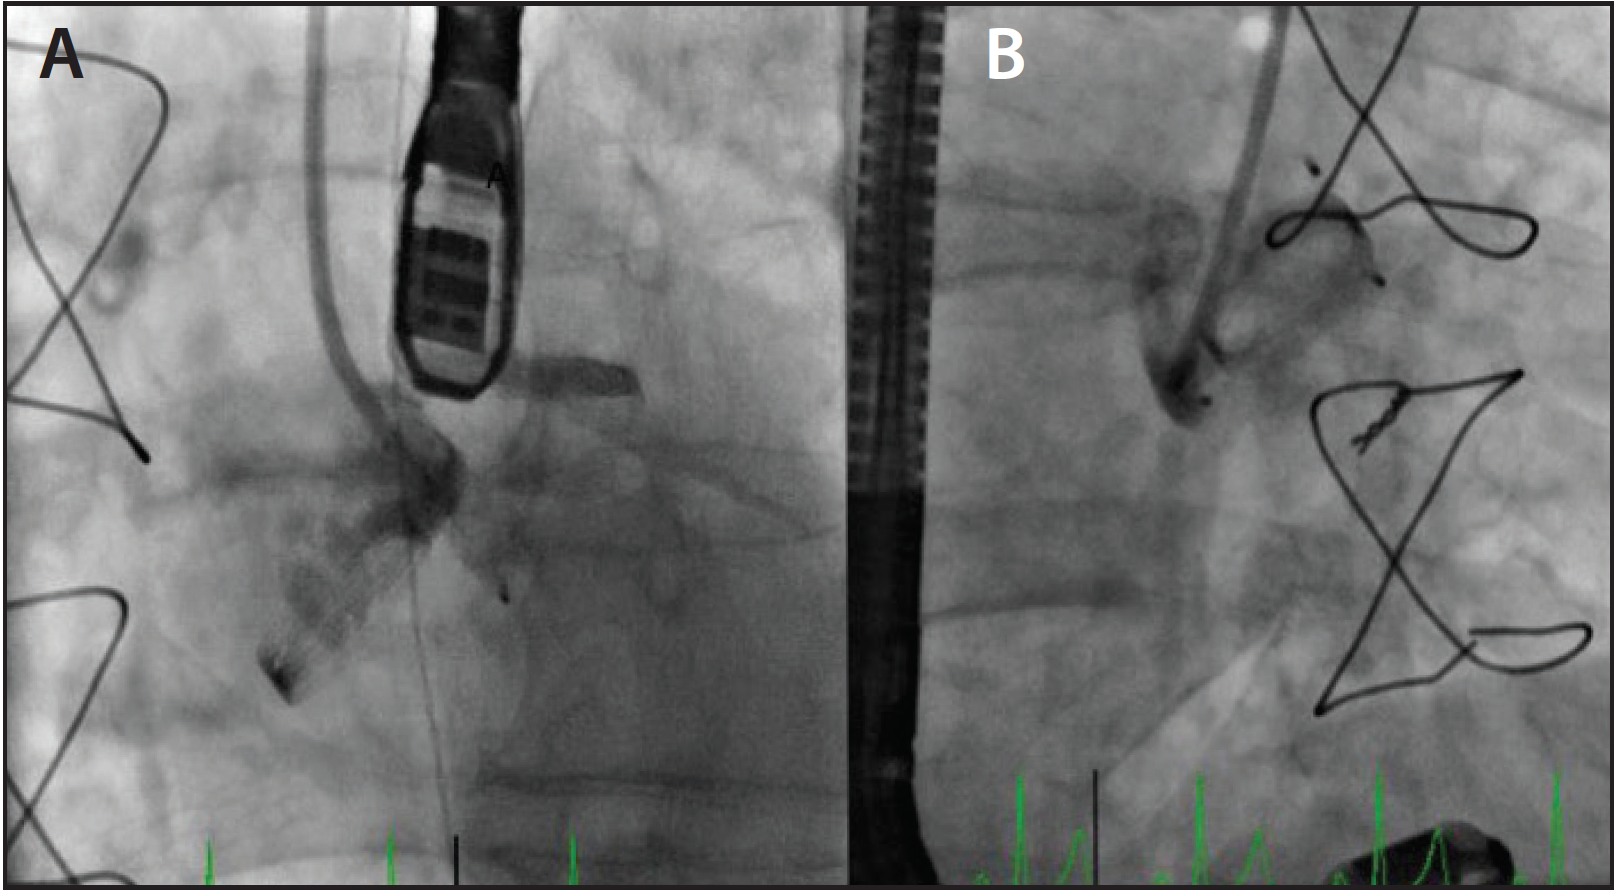

In other instances, we have used a combination of radial artery and FV access or a combination of FA and AVA that can be customized for the anatomy of each individual patient (Figure 5). With the miniaturization of the device profile to a 12-mm diameter, the Amplatzer VSD occluder (St. Jude Medical, Inc.) can be deployed through a 7-F sheath. The basilic vein access is preferred over cephalic vein access. Ultrasound guidance or the levophase technique can be used to determine a fairly large superficial basilic vein.9 As the veins expand, a sheath (> 7 F) can be used through the basilic vein in appropriately selected patients, which will allow the use of a large VSD occluder.

Figure 5. LV angiography showing a complex, very high VSD with an aneurysmal septum (A). The VSD was crossed using a JR 4 catheter via the right RA with an angled hydrophilic wire (B). A VSD occluder was deployed from an FV approach (C). Final angiogram showing the closed VSD (D).